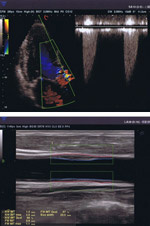

超音波診断装置

従来型より診断できる範囲が広がりました。

新たに心臓エコー(心エコー)・甲状腺エコー・下肢動脈静脈エコーの検査を行うことができるようになりました。

また、従来から行っていた腹部エコー・頸動脈エコーは、より詳しく診断できるようになりました。

超音波検査士の資格を持つ専門の臨床検査士が、月1回担当します。

・心臓エコー(心エコー)

心臓の状態を見る検査です。

心肥大、心拡大、心筋梗塞、心筋症、心臓弁膜症等の診断に役立ちます。

・頸動脈エコー

首の動脈で動脈硬化や狭窄の有無の診断を行います。

診断画像の例

クリックして拡大表示